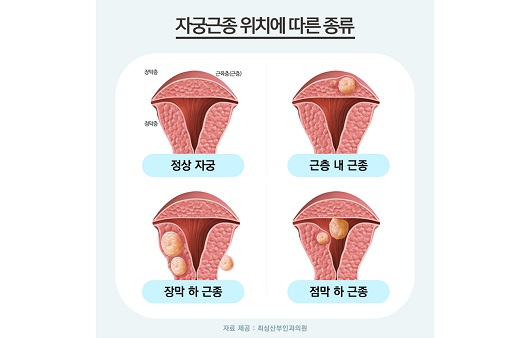

자궁에 발생하는 질환 중 대표적으로 알려진 것은 자궁근종과 자궁선근증, 다낭포성난소증후군 등인데 젊은 임신기 여성은 물론 중년 여성까지 연령에 상관없이 발생하고 있으며 그 중에서도 35세 이상 여성에게서 40~45% 정도가 겪고 있을 정도로 흔한 질환이 자궁근종이었습니다.발생한 위치에 따라 증상이 다르지만 경우에 따라서는 통증과 부정출혈을 동반할 수 있어 불임, 난임, 유산에 영향을 미치므로 임신 중인 여성이라면 반드시 정기적으로 자궁검진을 실시하여 예방과 적절한 치료가 이루어지도록 하는 것이 중요했습니다.자궁근종 하이프 시술은 자궁질환을 치료하는 가장 효율적인 방법으로 알려져 있으며 자궁선근증에도 활용되고 있었습니다.발생 위치에 따른 구분자궁근종은 자궁근육층에 근종이 발생한 것으로, 1cm 미만 크기부터 12cm 이상의 거대 근종까지 다양하게 확인됐습니다.개수나 위치에 따라 증상이 다르고 적절한 치료시기와 방법이 다르기 때문에 진단을 받는 과정에서 의료진의 숙련도와 임상경험 유무 및 검사장비와 치료장비 등 의료적 환경이 적절하게 갖춰져 있는지 확인하는 것이 중요했습니다.근층내근종가장 흔하게 발생하는 자궁근종으로 근육 중간 부위에 근종이 발생하여 자궁을 비대화시키고 내막을 확장시켜 복부압박감과 부정출혈 및 평소보다 많은 생리를 유발하였습니다. 장막하근종자궁 바깥쪽에 위치한 장막층에서 발생한 것으로 근종이 커지고 하복부에 대한 불쾌감이 심해져 근층 내 근종 다음으로 많이 발생했습니다.하복부가 볼록하게 돌출되어 빈뇨감과 잔뇨감을 느끼거나 배뇨 및 배변 장애를 겪는 경우가 자주 있었습니다. 점막하근종자궁 내 점막에서 발생하는 근종으로 크기에 관계없이 출혈이나 심한 생리통을 유발하고 임신에도 영향을 미치게 되었습니다.잦은 출혈로 빈혈을 일으키고 자궁 내부에 위치하기 때문에 불임은 물론 유산이나 조산에 결정적인 요인이 되는 경우가 많아 즉시 치료가 필요했습니다.자궁근종이 의심되는 증상발생 위치와 개수 및 크기에 따라 치료 여부가 달라졌고 자궁 건강에 미치는 영향도 모두 달랐습니다.하지만 자신의 몸에 있어서는 안 되는 비정상적인 조직인 것만은 변하지 않기 때문에 의심 증상을 알아두고 체크해서 조기 치료를 할 수 있도록 하는 것이 무엇보다 중요했습니다.생리통이 항상 심하게 느껴졌어요.생리 전 하복부 통증과 골반 안쪽 통증이 심했습니다.생리 중에 출혈량이 많았어요.생리 중 빈혈 증상을 경험했어요.부정출혈을 자주 경험했어요.아랫배가 중후해서 통증과 압박감을 잘 느꼈어요.아랫배가 나와서 가스가 잘 찼어요.잔뇨감과 빈뇨감으로 불편함을 느꼈습니다.아랫배와 복부에 단단한 막대기가 닿았어요.자궁근종 치료법근종의 종류나 임신력 등을 고려해서 치료 방법을 선택하는데 수술적인 치료인 복강경과 비수술적인 치료인 자궁내시경과 자궁근종 용해술 그리고 하프 시술이 있었습니다. 이 중 자궁근종 하이프 시술은 체력적 부담을 줄임과 동시에 자궁을 보존할 수 있는 방법으로 대중적인 인기를 얻고 있으며 자궁 손상을 피하고 자궁이나 임신력을 보존하는 데 최적화된 방법이라고 할 수 있습니다.하이푸는 고강도 집속 초음파 장비는 JC200D를 사용하는데, 다만 자궁근종과 자궁선근증 치료를 목적으로 개발된 장비였습니다. 고강도 집속 초음파가 복부를 투과해 근종만을 찾아 고온에서 괴사를 유도함으로써 실시간 모니터링과 1.1mm 미세초점으로 움직이면서 타겟팅할 수 있어 근종의 위치와 크기에 관계없이 정확하게 치료할 수 있었습니다.비용이 아닌 결과가 중요한 치료여성에게 자주 발생하는 자궁근종이지만 제대로 치료하지 않으면 재발이 잦아 임신이나 출산에 악영향을 미칠 수 있었습니다. 따라서 비용적인 부분을 보기 전에 다양한 임상 경험을 가진 의료진이 진료를 책임지고 있는지 자궁을 살릴 수 있는 하이프를 우선시하는지 먼저 알아보는 것이 좋았습니다.레아산부인과에서는 병변 위치를 명확히 확인할 수 있도록 시술 전후 2회에 걸쳐 MRI 촬영을 실시하였으며, 산부인과 전문의이자 가톨릭대학교 외래교수인 이경숙 원장이 직접 진료하고 있는 만큼 1:1 맞춤 치료로 건강한 생활과 건강한 신체를 유지하기 위해 필요한 지원을 받을 수 있었습니다.여성에게 자주 발생하는 자궁근종이지만 제대로 치료하지 않으면 재발이 잦아 임신이나 출산에 악영향을 미칠 수 있었습니다. 따라서 비용적인 부분을 보기 전에 다양한 임상 경험을 가진 의료진이 진료를 책임지고 있는지 자궁을 살릴 수 있는 하이프를 우선시하는지 먼저 알아보는 것이 좋았습니다.레아산부인과에서는 병변 위치를 명확히 확인할 수 있도록 시술 전후 2회에 걸쳐 MRI 촬영을 실시하였으며, 산부인과 전문의이자 가톨릭대학교 외래교수인 이경숙 원장이 직접 진료하고 있는 만큼 1:1 맞춤 치료로 건강한 생활과 건강한 신체를 유지하기 위해 필요한 지원을 받을 수 있었습니다.희아산부인과의원 서울특별시 강남구 강남대로 340 4층희아산부인과의원 서울특별시 강남구 강남대로 340 4층희아산부인과의원 서울특별시 강남구 강남대로 340 4층희아산부인과의원 서울특별시 강남구 강남대로 340 4층희아산부인과의원 서울특별시 강남구 강남대로 340 4층희아산부인과의원 서울특별시 강남구 강남대로 340 4층